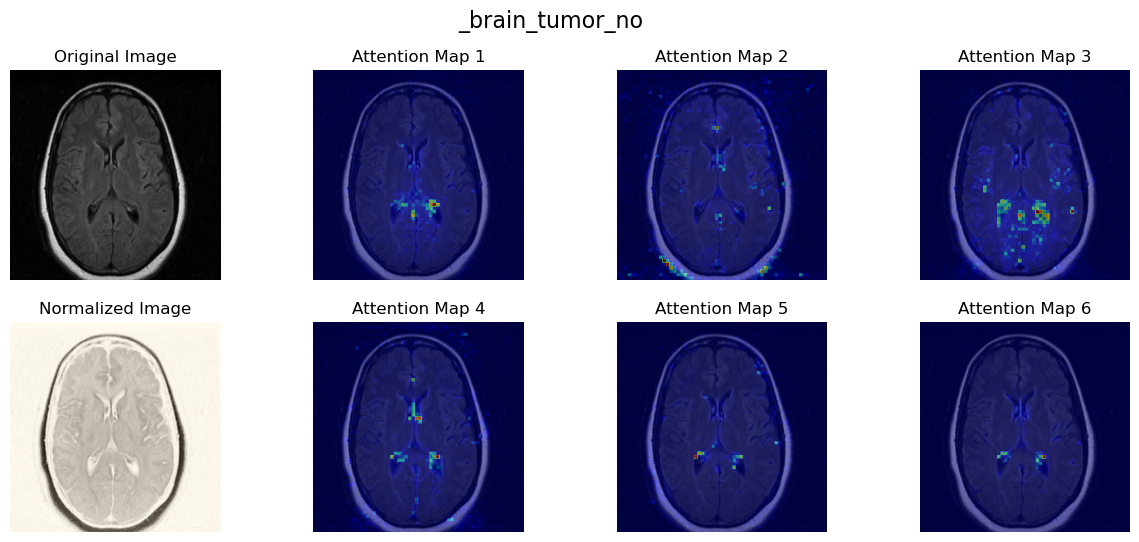

Normal brain에 대한 heatmap!

Malignant 병변이 명확하게 보이는 하나의 Brain tumor image를 기반으로,

Epoch에 따라서 Visition transformer의 Attention을 heatmap으로 나타내보았다.

epoch가 진행될 수록, 한 이미지에서 환자의 특징을 가장 잘 나타내는 Lesion에 집중을 하는 것을 볼 수 있다.

AI모델이 Local / Global view에서 동일한 feature를 뽑게 하는 것은,

결국 view에 따라서 마구잡이로 바뀌는 background noisy가 아닌

사진에서 가장 중요한 object를 집중하게 만들게 된다.

비록 아무런 Label 없이 이미지만 학습한 것이지만, 훌륭히 중요위치를 살펴본다.